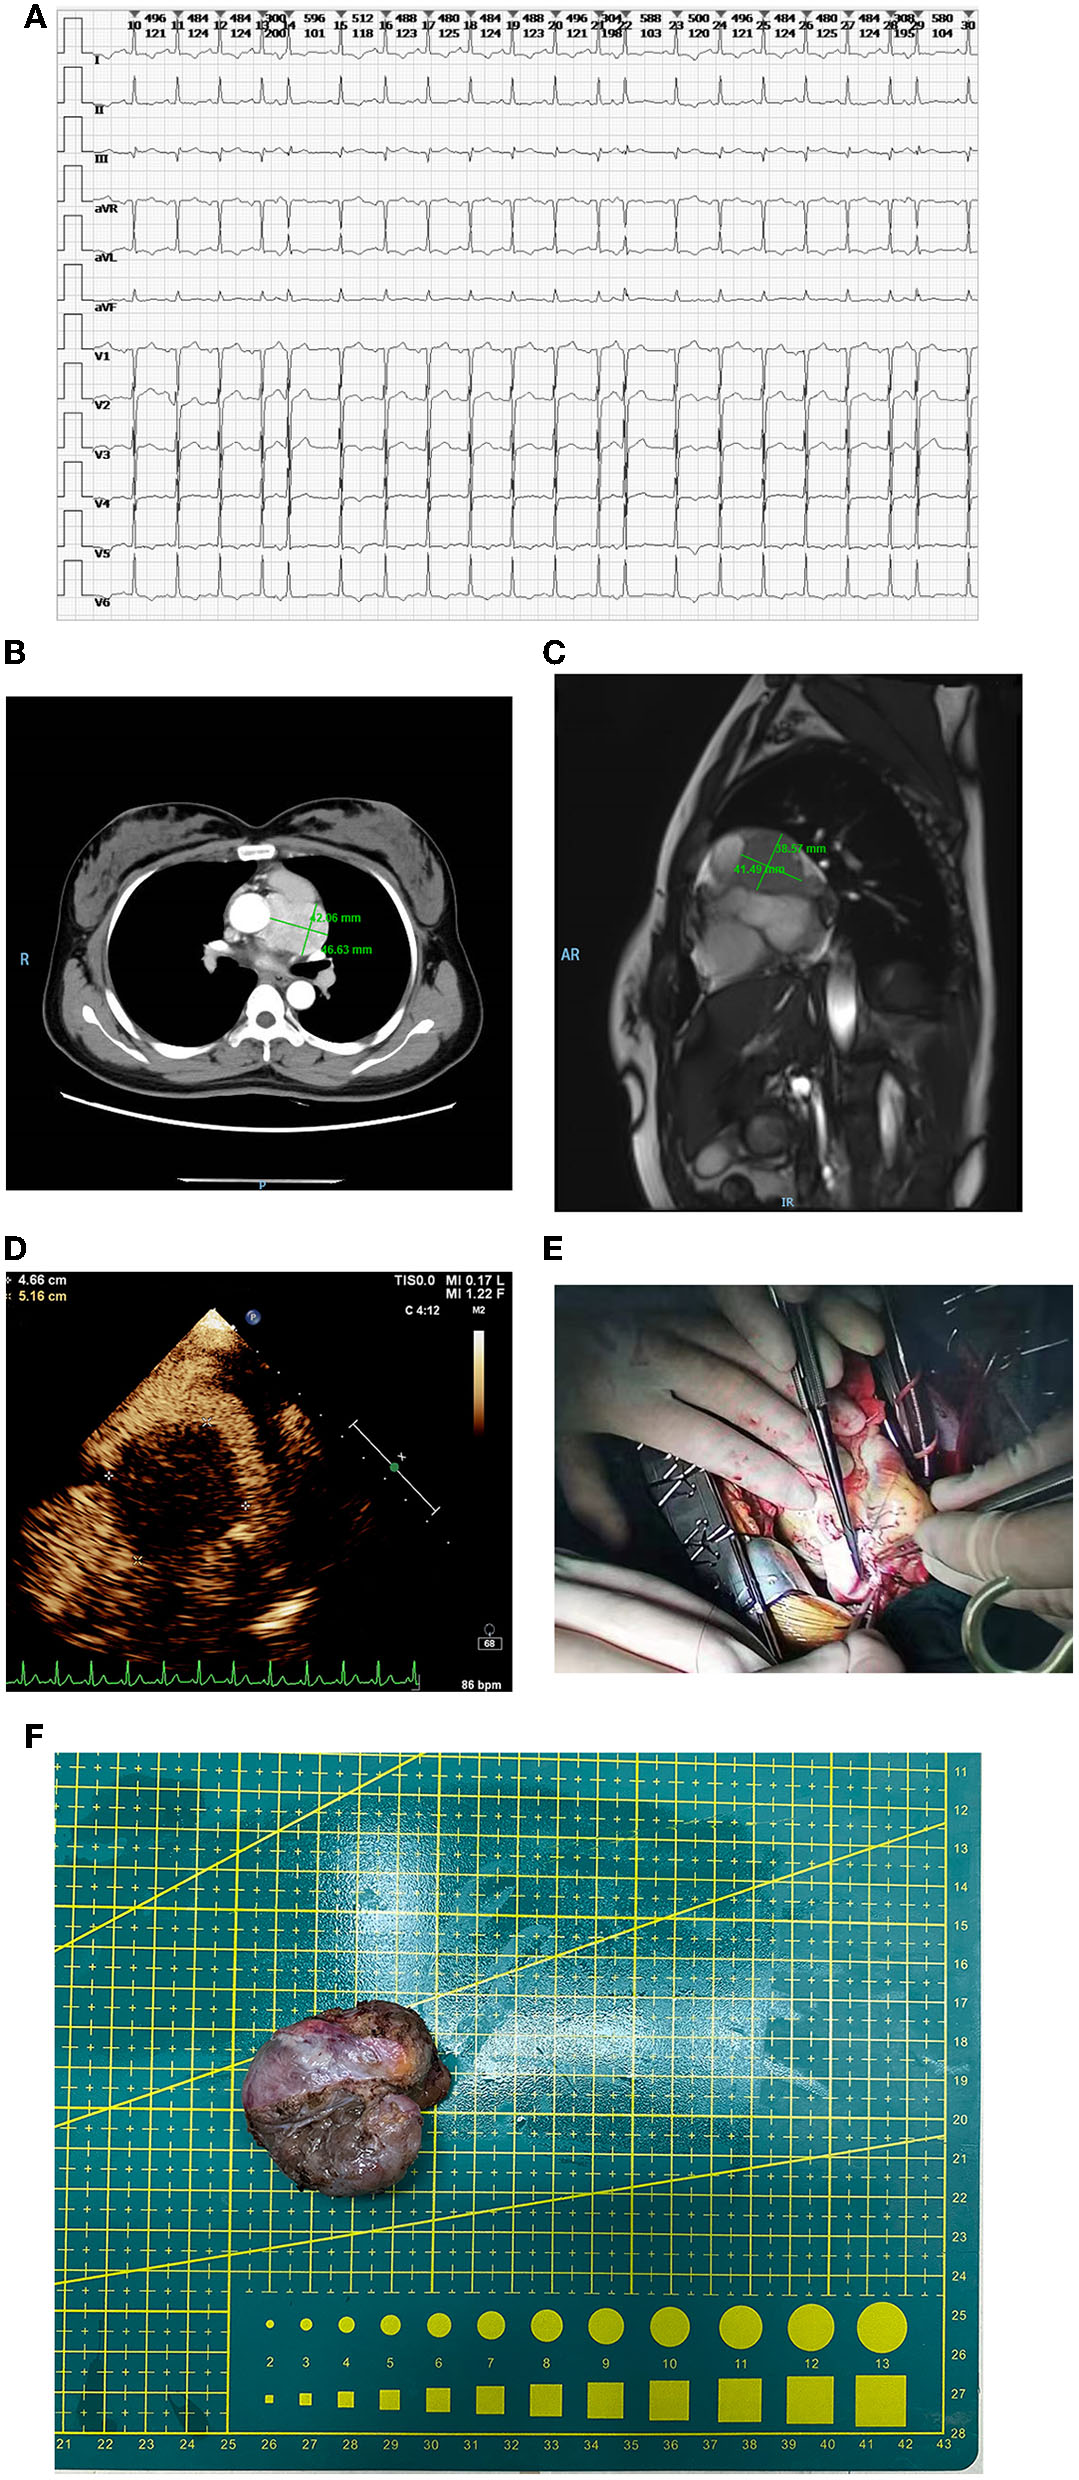

When at admission, tachycardia was found by electrocardiogram (Figure 1A). Based on the findings from the contrast-enhanced CT, it was demonstrated that a mass of 46 × 42 mm with serious adhesion to the surrounding aorta located at the root of the aorta in the middle mediastinum and the left main coronary was also involved (Figure 1B).

(A) Tachycardia in electrocardiogram at admission. (B) The mass in the contrast-enhanced CT. The size was 46 × 42 mm and serious adhesion between the aorta and the mass was found. Also, the involved left main coronary was observed. (C) The mass in the MRI. Both the root of the aorta and left main coronary were involved, however, the myocardium was free from involvement. (D) The mass in the echocardiography. The mass was fully perfused through mini-vascular circulation. (E) The repairing of the pulmonary artery. (F) The removed mass.

In MRI, it was confirmed that both the root of the aorta and left main coronary were involved, however, the myocardium was free from involvement (Figure 1C). In accordance with the echocardiography, the mass was completely perfused through mini-vascular circulation (Figure 1D). After exclusion of adrenal pheochromocytoma with the absence of any abnormal images found in bilateral adrenals, the final diagnosis of primary cardiac paraganglioma was confirmed comprehensively in accordance with the objective results from imaging and lab tests indicating the elevated catecholamine. The α and β receptor blockers were selected as preoperative agents for hypertension control and multidisciplinary consultants were performed, including gynecology and urology for preoperative assessment.

Peripheral cardiopulmonary bypass (CPB) was established via the femoral artery and vein. Once CPB started, the median sternotomy was selected. After surgical field exposure, it was found that the mass with the visual size of 65 mm located at the outflow tract of the right ventricle besides the main pulmonary artery was involved seriously. The blood supplement was distributed fully around the mass. Cardiac arrest was maintained using HTK cardioplegia after ascending aorta clamping when the temperature is lower than 35°C. Given the complicated mass-related anatomical changes, extended lesion resection, reconstruction of the pulmonary artery, and coronary artery bypass grafting (CABG) were processed simultaneously. The surgical separation of the mass began at the anterior wall of outflow of the right ventricle. The main pulmonary artery was opened to expose the pulmonary valve due to serious adhesion between the mass and the right ventricle. Then, the separation of the posterior wall of the main pulmonary artery was continued cautiously. Meanwhile, the proximal end of left main coronary was also damaged due to severe involvement by the mass. After the mass was removed completely, a bovine pericardial patch of reasonable size was used to repair the pulmonary artery (Figures 1E,F).